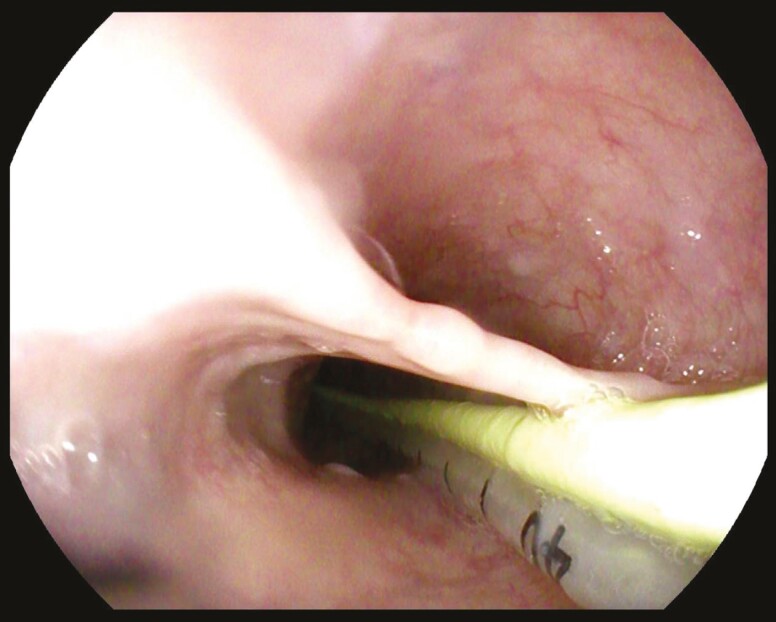

A rare case of oesophageal mucosal bridge.

一个罕见的食道粘膜桥病例。